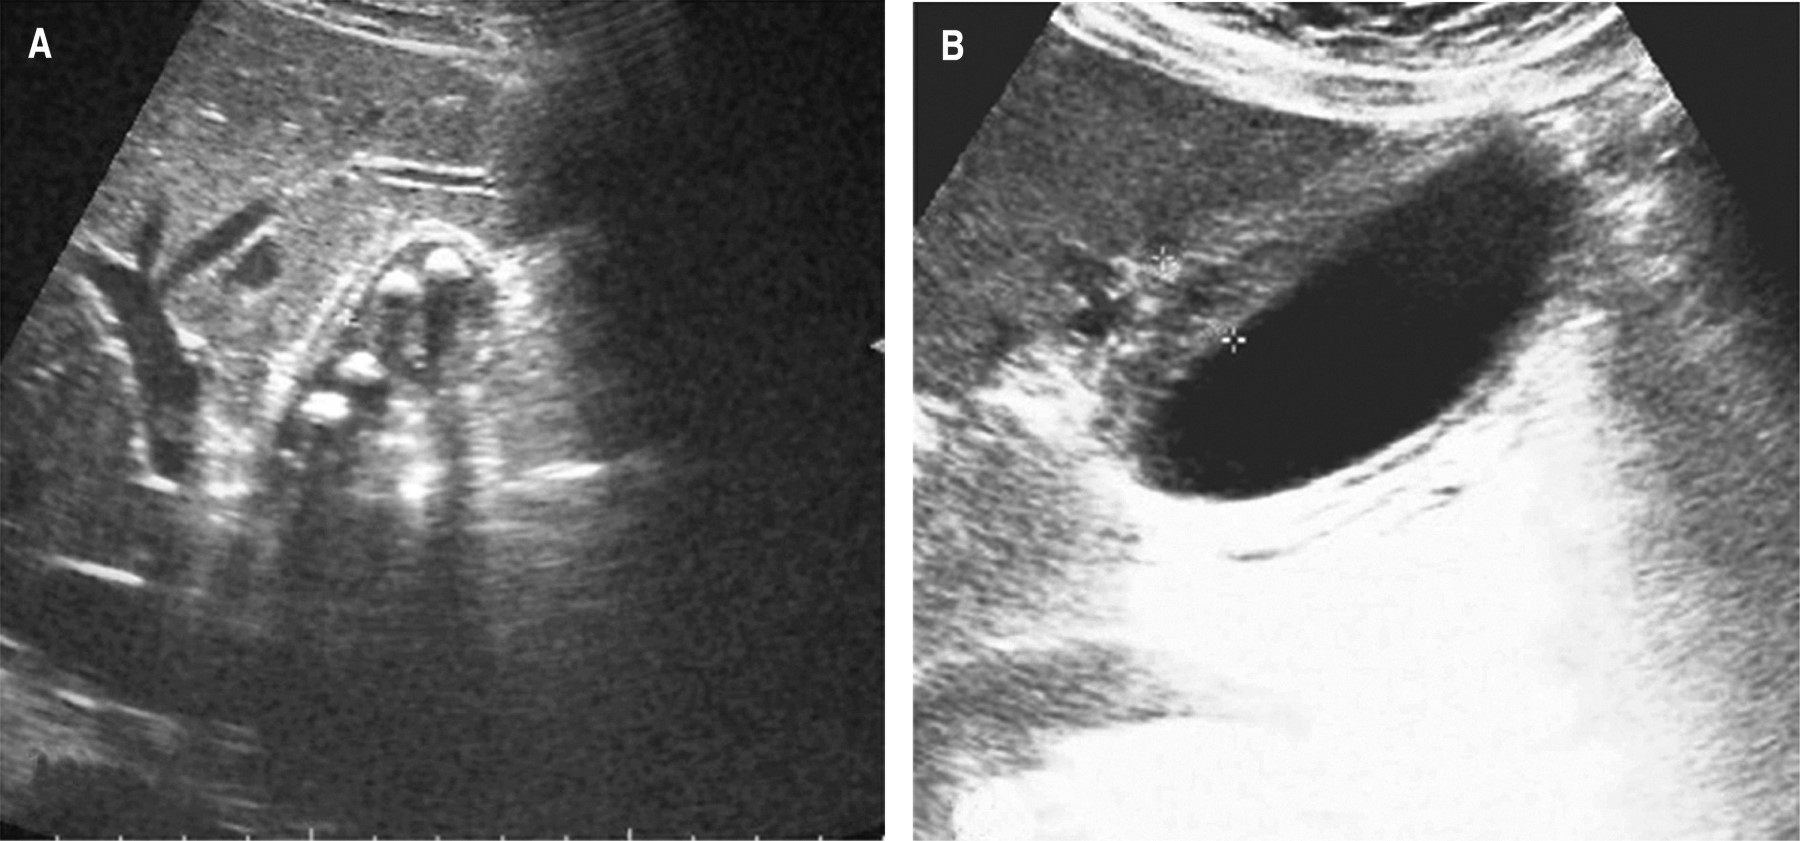

Upon admission, all patients underwent imaging studies for suspected acute cholecystitis (abdominal ultrasonography and/or abdominal tomography). In all patients, the gallbladder wall thickening of more than 5 mm (mean 8.96 mm, range 5-16 mm) was corroborated, and signs of acute cholecystitis (criteria TG-18) or structural alterations were ruled out. Differences between acute cholecystitis and gallbladder edema in the abdominal ultrasound are shown in Figure 1, and differences in the CT scan are shown in Figure 2, respectively.

Figure 2